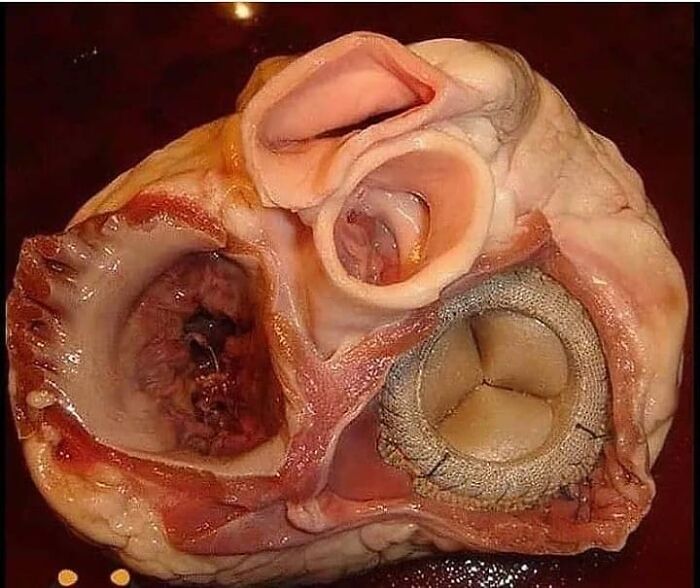

Heart Valve